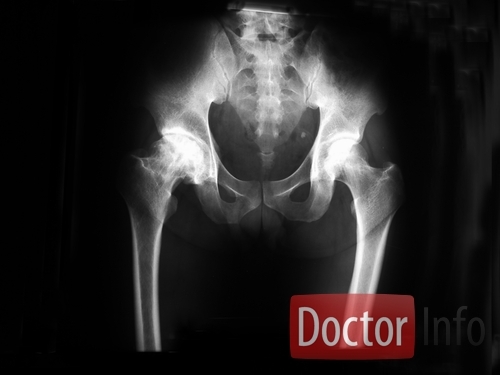

ДИАГНОСТИКА

Диагностика АН начинается с изучения жалоб пациента, истории заболевания и физикального исследования: осмотра, пальпации сустава и изучения его функции (угол отведения, сгибания конечности и др.). Для уточнения диагноза проводится рентгенография тазобедренного сустава, радиоизотопное сканирование (сцинтиграфия), МРТ.

Медицинские процедуры, проводимые при заболевании асептический некроз головки бедренной кости: Биохимический анализ крови, Клинический анализ крови, Спиральная компьютерная томография, Магнитно-резонансная томография, Рентген, Сканирование костей